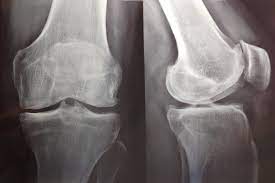

Antidepresivos para la artrosis de cadera y rodilla

Hay evidencia de certeza alta de que el uso de antidepresivos para la artrosis de rodilla produce una mejoría insignificante desde el punto de vista clínico en el dolor medio y la funcionalidad. Sin embargo, un pequeño número de personas tendrá una mejoría importante del 50% o más en el dolor y la funcionalidad. Este hallazgo fue consistente en todos los ensayos. El dolor en la artrosis se podría deber a diversas causas que difieren entre las personas. Es posible que la causa del dolor que responde a este tratamiento solo esté presente en un pequeño número de personas. Hay evidencia de certeza moderada de que los antidepresivos tienen un pequeño efecto positivo sobre la calidad de vida, con heterogeneidad entre los ensayos. Cochrane Database of Systematic Reviews 21 de octubre de 2022